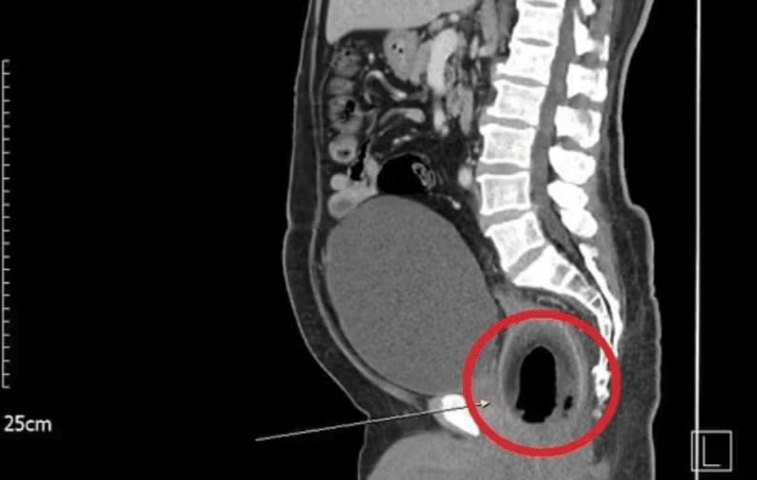

🥥NO RETO - O paciente de 56 anos não teve a identidade revelada, informações acerca da data em que o procedimento foi realizado e o motivo para a fruta estar no ânus também não foram divulgadas. O caso saiu no jornal British Journal of Surgery, e mostra o coco alojado no reto do homem.

📏TAMANHO - A fruta tinha cerca de 9 cm de comprimento, e estava impedindo o homem de urinar e defecar. Foi necessário uma laparotomia para extrair o coco de dentro do paciente. A cirurgia consiste na abertura do abdômen. Em casos assim é necessário de seis a oito semanas de recuperação.